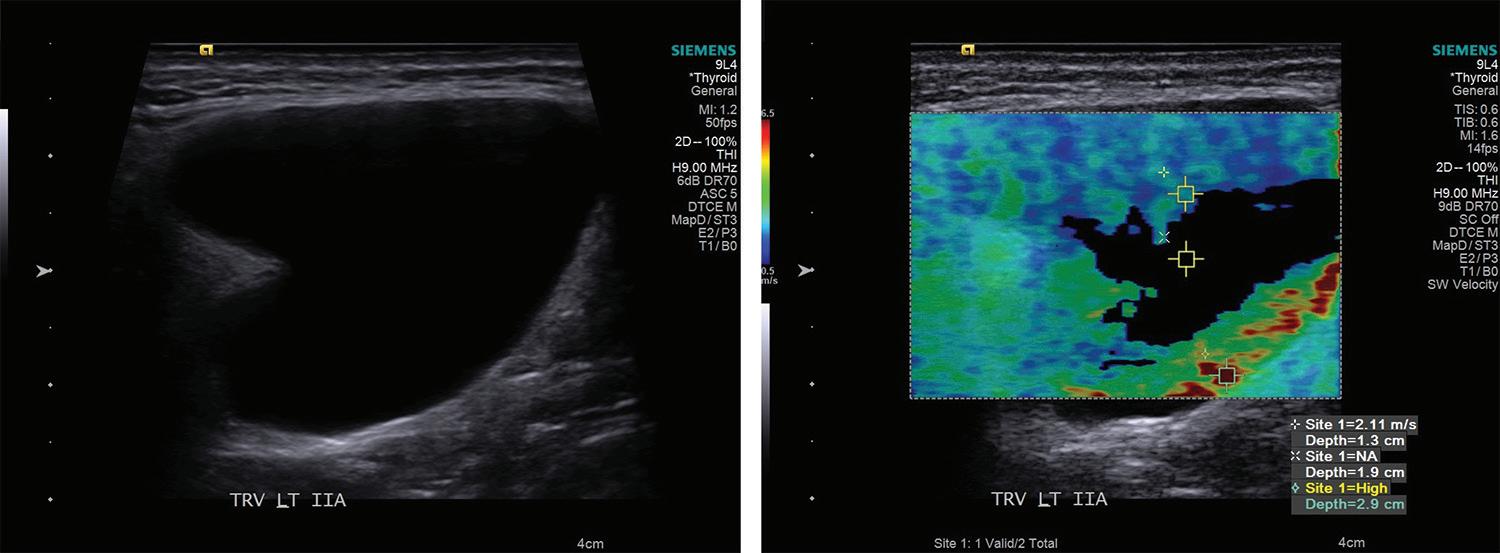

19. Valtonen HJ, Poe DS, Heilman CB, Tarlov EC. Endoscopically assisted prevention of cerebrospinal fluid leak in suboccipital acoustic neuroma surgery. Am J Otol 1997;18(3):381-5.

20. Magnan J, Barbieri M, Mora R, et al. Retrosigmoid approach for small and medium-sized acoustic neuromas. Otol Neurotol 2002;23(2):141-5.

21. Göksu N, Bayazit YA, Bayramoglu I, et al. Surgical exposure in retrosigmoid approach: Do we need cerebellar retractors? Surg Neurol 2006;65(6):631-4.

30 www.entjournal.com ENT-Ear, Nose & Throat Journal January/February 2018

KOUHI, ZARcH, POUyAN

Elastography as a potential modality for screening cervical lymph nodes in patients with papillary thyroid cancer: A review of literature

Abstract

Papillary thyroid cancer often presents with cervical lymph node involvement and has a high incidence of recurrence, which requires routine follow-up with ultrasound imaging. Elastography is a novel ultrasound technique that has been demonstrated to be effective clinically in detecting tissue pathology in areas such as the liver and breast. Preliminary data suggest that it may be effective in screening tissues in the neck for malignancy, specifically cervical lymph nodes. However, diagnostic criteria and elastographic techniques vary significantly among the studies we have reviewed, which all tend to focus on populations of patients with many different types of primary malignancies. Further research is required on the feasibility of creating standardized and reproducible clinical criteria in a specific patient population. To study the clinical utility of elastography in cervical lymph nodes, patients with diagnosed papillary thyroid carcinoma may serve as an ideal population because of their need for ultrasound surveillance and the propensity of papillary thyroid cancer to metastasize to and recur in cervical lymph nodes. We will review the limitations, techniques, and reported clinical utility of elastography on cervical lymph nodes and its potential as a screening modality for papillary thyroid cancer.

Introduction

Papillary thyroid carcinoma (PTC) is the most common malignancy affecting the thyroid. Approximately 50% of patients with PTC have lymph node involvement when diagnosed, with up to 20% having an en-